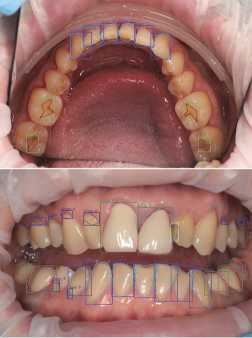

The dataset is primarily intended to solve the Instance Segmentation problem [16], therefore, in addition to the bounding boxes, carefully marked masks are available for each pathology. Examples of the marked images are shown in Fig. 1.

Fig. 1. Examples of photographs of the oral cavity with markings